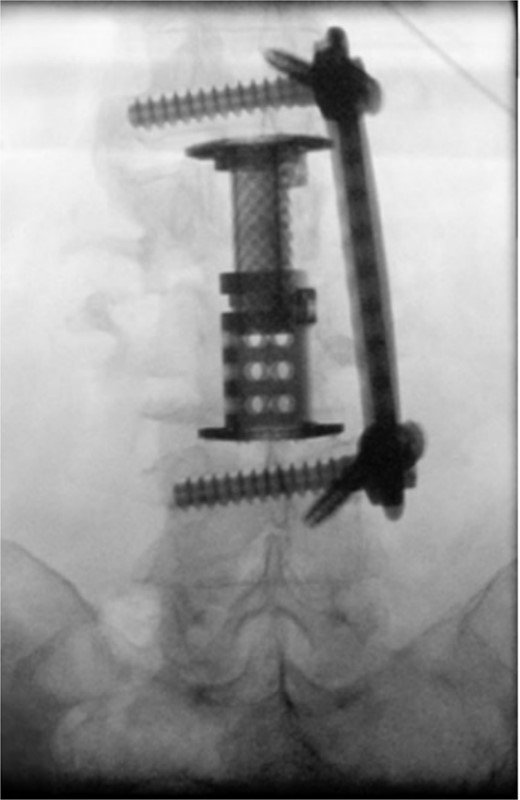

The patient was placed in the operating room for anterior lumbar interbody fusion via thoracoabdominal (TA) incision for retroperitoneal exposure. The patient was placed in the right-lateral decubitus position. The 10th rib interspace was identified, and a curvilinear incision was made from the midaxillary line and extended anteriorly and inferiorly toward the umbilicus. The retroperitoneal plane was entered, and the 11th rib was cut and morcellated for lumbar cage placement. The diaphragm was divided radially with electrocautery to further expose the abdominal cavity and retroperitoneal space. The lateral border of the psoas muscle was exposed and dissected into the anterior vertebrae L1–L4. The aorta and abdominal viscera were retracted toward the patient’s right side using an Omni retractor. Copious necrotic tissue and caseating granulomas were removed. The L2–L3 vertebrae were exposed, corpectomy was performed, and a titanium cage was placed with a plate spanning from L1 to L4 (Fig. 2A and B). To achieve added stability, a second surgery for posterior percutaneous screw placement without lumbar fusion was performed (Fig. 3). The patient recovered without complications and was subsequently discharged to a skilled nursing facility, and ultimately home. At the 1-month follow-up visit, the patient’s TA incision had completely healed, and there was no evidence of recurrent infection.

Intraoperative fluoroscopy depicting two pedicle screws posteriorly placed in a percutaneous fashion with a 5.5 × 100 mm2 rod placed in the pedicle tulips.